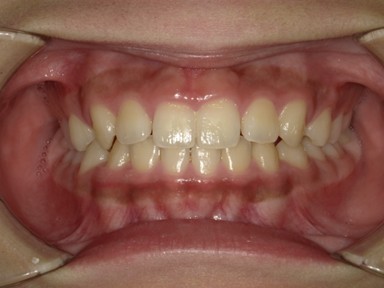

| 主訴 | 生えてきた下の永久歯が曲がっている。これから生えてくる歯も並ぶか心配。 |

| 治療内容 | マイオブレース(J1 → J2 → K3 → T4)と拡大床(BB1)を使用しました。 口腔周囲筋トレーニングも併用しました。 (抜歯:なし、ワイヤー矯正:使用せず) |

| 治療期間 | 78ヶ月(永久歯列完成まで経過観察) ※治療開始から2年間は毎月通院し、その後は3~4か月に1回の頻度で経過観察を継続。 |

| 想定されたリスク | 抜歯や全顎ワイヤー矯正のリスクがありました。 |